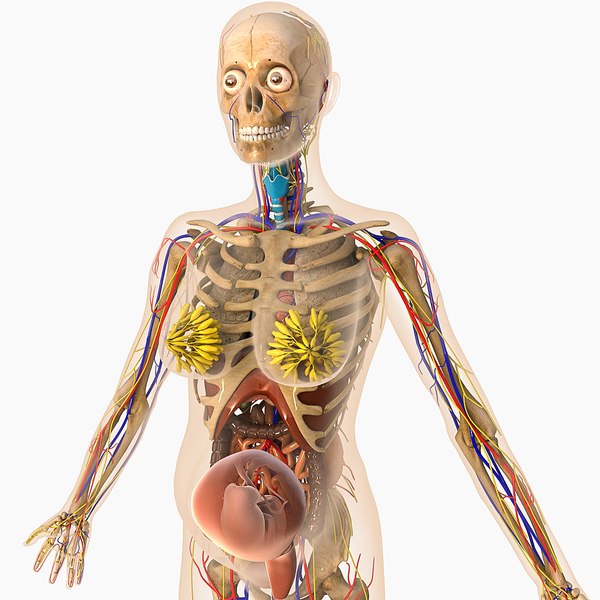

Физиология беременности: строение органов